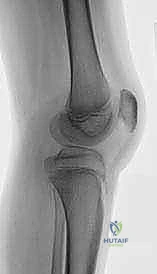

- الأشعة السينية البانورامية (Scanogram): أخذ صور للطرفين السفليين بالكامل أثناء الوقوف لتقييم المحور الميكانيكي.

- الأشعة الجانبية للركبة: ضرورية جداً لقياس نسبة (Insall-Salvati ratio) لتشخيص وتحديد درجة "ارتفاع الرضفة" (Patella Alta).